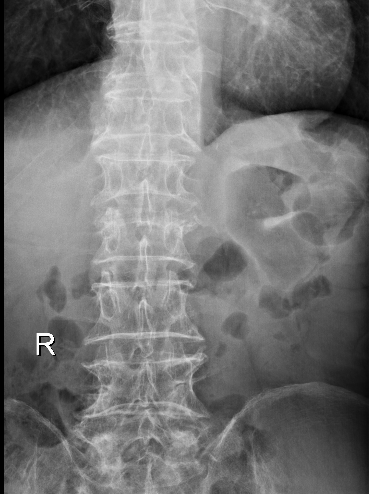

术后

术后